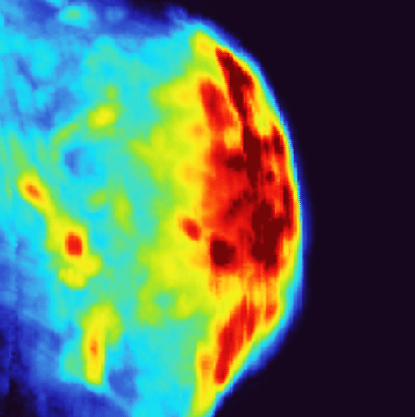

Tri Vu was a PhD student in the lab of Junjie Yao, the Jeffrey N. Vinik Associate Professor of Biomedical Engineering, where he was working on photoacoustic tomography, an imaging technique that involves shooting a laser into tissue and measuring the resulting ultrasonic wave to create colorful images. At the time, Vu had been creating a full-ring array for small animal imaging that he dubbed photoacoustic computed tomography (PACT).

Canning had heard about Vu’s technology and was curious about how it would pair with his nanostars. The feeling was mutual for Vu. In initial experiments, the team found that Vu’s imaging system could easily track the accumulation of Canning’s nanostars in the targeted tumors and tissues throughout the animals. They also discovered that the thermal sensitivity of photoacoustic imaging enabled the team to more precisely measure the temperature of the nanostars and surrounding tissue.

Canning and Vu tested the efficacy of their system in a mouse model for bladder cancer using an updated version of the gold nanostars. Canning’s new design encases each nanostar within a hollow gold shell that stabilizes the star’s branches as they heat, preventing them from melting into spheres. When coupled with Vu’s PACT system, the team was easily able to detect and image the nanostars and monitor the progress of the photothermal treatment. By more precisely monitoring the temperature, the team was able to observe the ideal temperature dosage needed to activate the nanostars and destroy cells.